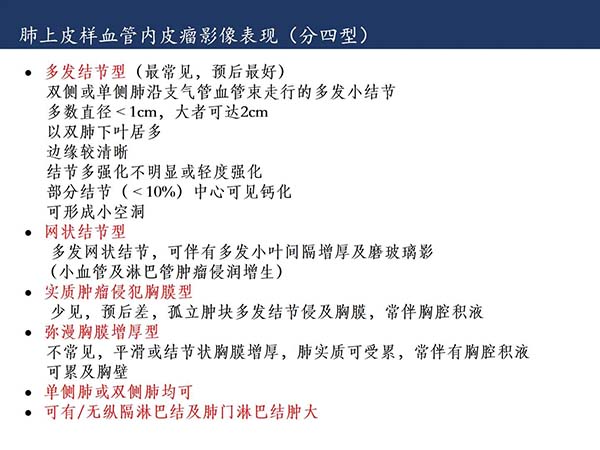

【杨柳科普】肺上皮样血管内皮瘤的影像表现